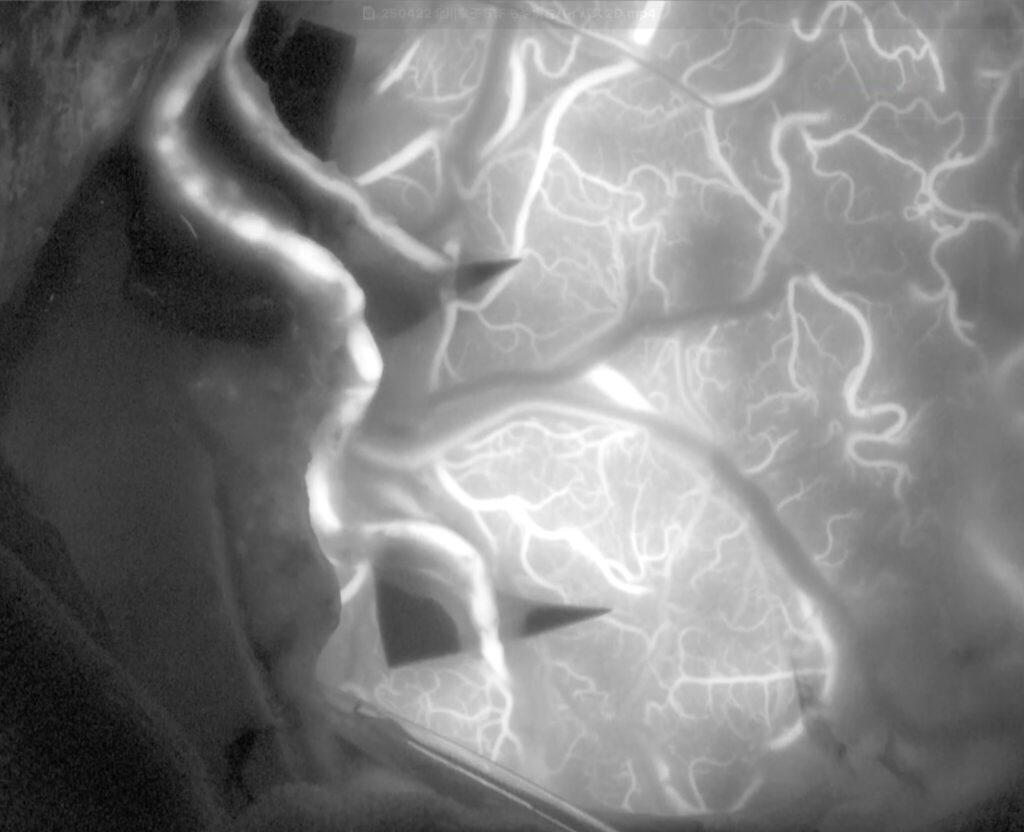

51歳女性の脳梗塞と脳室内出血を続けて起こした左片側もやもや病の患者さんをバイパス手術しました。STAがgaleaから外に出てGaleaの外に枝を出していたため皮弁翻展時にSTA頭頂枝が切れてしまい、端端吻合をしてからバイパスに用いました。2本とも無事開通しました。脳血流が著明に低下していたので術後の過灌流が心配で厳重な術後血圧管理を行いましたが、幸い順調な回復を見せています。

51歳女性の脳梗塞と脳室内出血を続けて起こした左片側もやもや病の患者さんをバイパス手術しました。STAがgaleaから外に出てGaleaの外に枝を出していたため皮弁翻展時にSTA頭頂枝が切れてしまい、端端吻合をしてからバイパスに用いました。2本とも無事開通しました。脳血流が著明に低下していたので術後の過灌流が心配で厳重な術後血圧管理を行いましたが、幸い順調な回復を見せています。